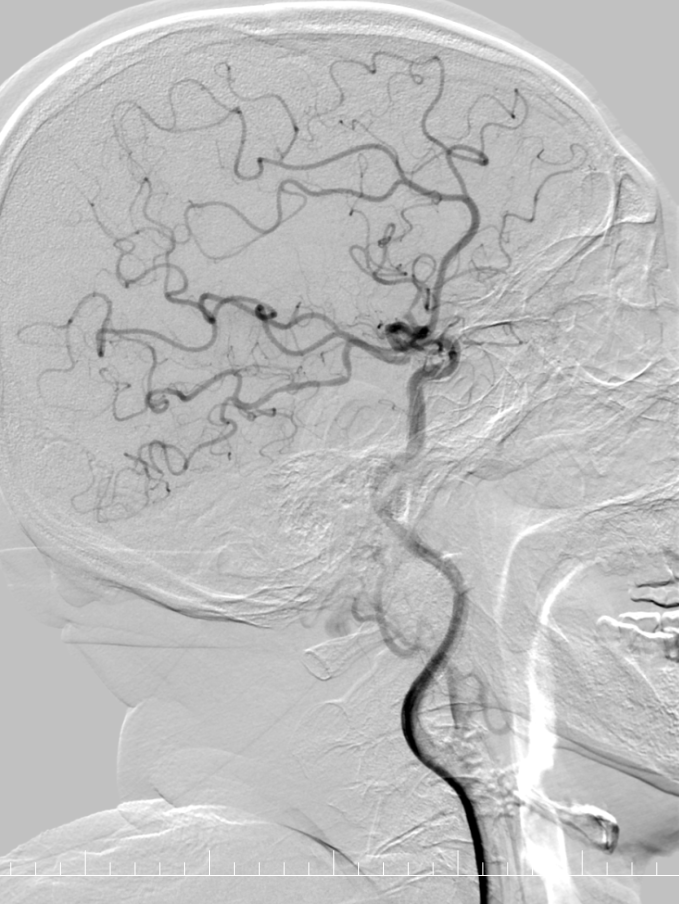

造影提示右侧大脑中动脉M2段下干闭塞。

动脉长鞘怎么置入有励可说|Locaste 088励楷长鞘及Tarvos微导丝在右侧大脑中动脉M2段取栓术中的应用_https://www.jmylbn.com_新闻资讯_第10张

动脉长鞘怎么置入有励可说|Locaste 088励楷长鞘及Tarvos微导丝在右侧大脑中动脉M2段取栓术中的应用_https://www.jmylbn.com_新闻资讯_第11张